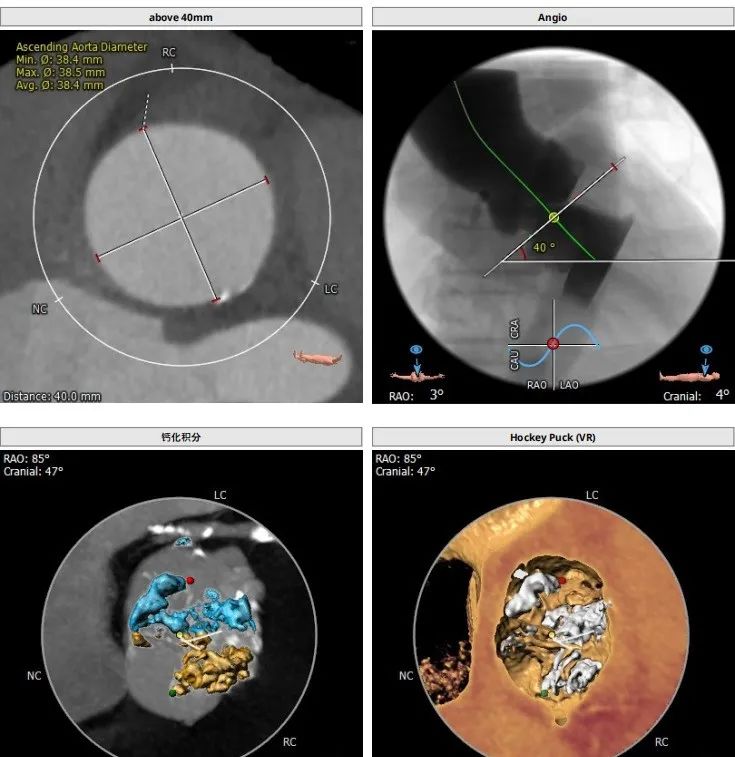

患者为TYPE0二叶瓣,重度钙化,术前可见瓣周突出物,怀疑囊肿,瓣环23.8,LVOT25.5,鱼嘴开口22.8,预计瓣口开口22.3,STJ33.9,窦部空间大,左右冠高度分别为19.9和21.5,预计18号球囊预扩。